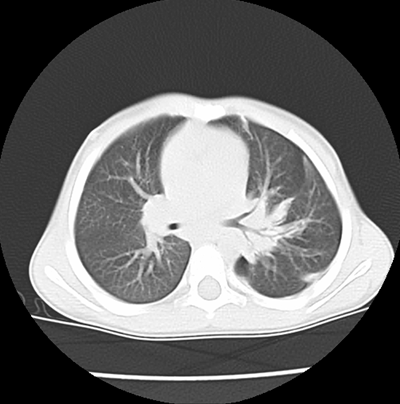

We asked for a Chest CT scan